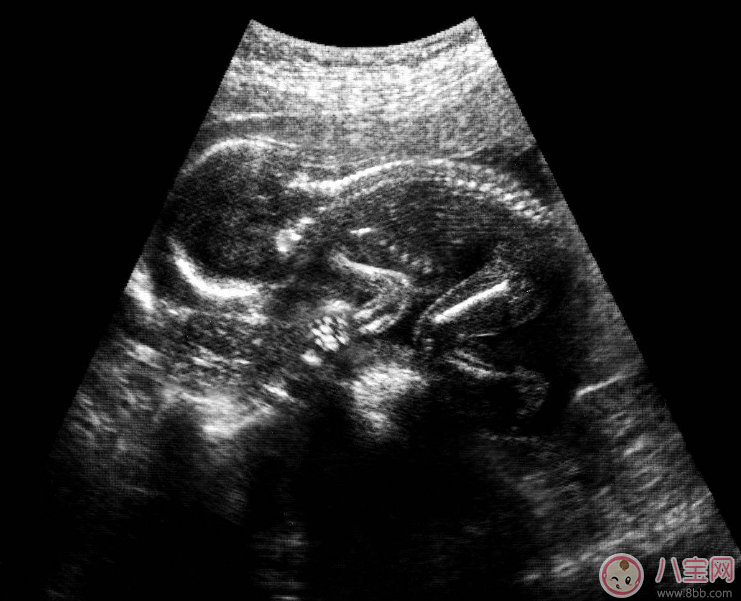

如果真的有危及生命、必須做X光片的情況,孕媽媽還可以多做一層保護,就是腹部圍上鉛服,另外就是照射時間盡可能短。X光對胎兒的影響主要與照射劑量和照射部位有關,照射胸部、手腳等遠離胎兒的部位比照射腹部、骨盆等離胎兒近的部位影響小。而在重點部位穿上鉛服,可防止射線穿過,一定程度上減少輻射傷害。同樣的部位,做CT的輻射量幾乎是拍10張X線片的輻射量。因此,CT是更要避免接觸的檢查,大原則仍然是:除非危及生命且不做不可的才做。B超安全性最高但沒必要做太多超聲檢查是一種無創傷性的影像檢查技術,在整個孕期被認為是安全的,是妊娠期影像學檢查的首選方式。但畢竟一種能量形式的輸出,并非多多益善,做得過多沒有必要。健康、正常的孕媽媽整個孕期的超聲檢查可這樣安排: